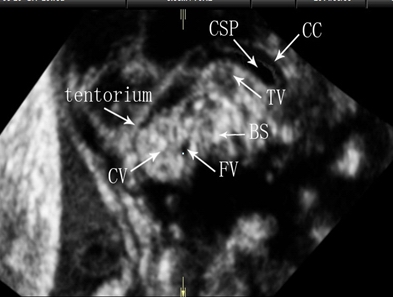

注:CV为小脑蚓部 图1 经腹三维超声显示正常胎儿小脑蚓部三个正交平面声像图

注:tentorium为小脑幕;CV为小脑蚓部;FV为第四脑室;CC为胼胝体;CSP为透明隔腔;TV为第三脑室;BS为脑干; 图2 经腹三维超声C平面显示正常胎儿小脑蚓部正中矢状切面声像图